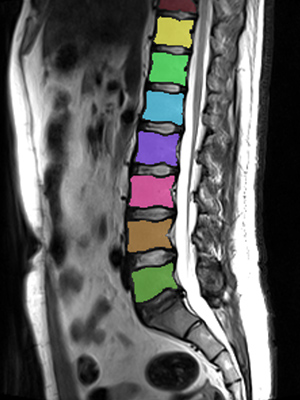

We trained and evaluated the method with five sets of CT and MR scans that visualize the spine. Reference segmentation masks for four of these datasets are publicly available, which allowed for a comparison with other publications that used the same data. Examples of images from the datasets are shown in Figure 3.

Similar performance was achieved for vertebra segmentation in various CT datasets with an average Dice score of and for vertebral body segmentation in an MR dataset with an average Dice score of . Surface distances were lower on CT images compared to MR images ( vs. ), however, there were also fewer training scans available in the MR dataset. Figure 4 illustrates the magnitude of differences of the automatic segmentations from the ground truth segmentations.

(a) Low-dose chest CT

(b) Lumbar spine CT (xVertSeg.v1 dataset)

(c) Lumbar spine MR

In the CT datasets, the segmentation was more accurate on high-resolution dedicated spine scans of healthy subjects compared with low-dose low-resolution chest CT scans and scans of subjects with in some cases severe compression fractures. This is also visible in the segmentation performance stratified by vertebra (Figure 5). Segmentations were more accurate for the lumbar (L1-L5) than for the thoracic vertebrae (T1-T12), which are covered by the more challenging low-dose chest CT scans. Outliers among the lumbar vertebrae correspond to vertebrae from the xVertSeg.v1 dataset, which features a number of severely deformed lumbar vertebrae that are particularly challenging to segment.